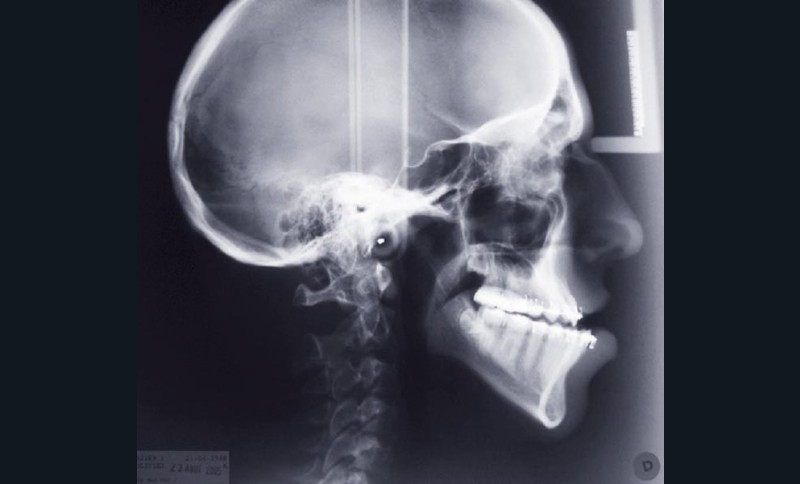

Olivier se présente à l’âge de 12 ans avec une classe III squelettique à prédominance mandibulaire, accompagnée d’une hyperdivergence et d’une endomaxillie responsable des inclusions des canines supérieures à forte obliquité. Une phase d’expansion est réalisée afin de permettre une augmentation du périmètre de l’arcade et la verticalisation des germes des canines. L’expansion permet en effet une normalisation transversale mais ne permet pas de réaliser la mise en place des canines. Les extractions des prémolaires sont alors effectuées et une préparation primaire de l’arcade supérieure par multi-attaches avec désinclusions et tractions des canines est réalisée.

Une pause thérapeutique est ensuite entamée jusqu’à la fin de croissance soit 18 ans. Une poursuite du traitement par préparation secondaire à la chirurgie orthognathique bimaxillaire est programmée.

Les mouvements de décompensations sagittales et transversales sont réalisés à l’aide des tractions inter-arcades. La réévaluation céphalométrique et l’analyse des moulages confirment l’indication d’une chirurgie maxillaire de propulsion et d’une chirurgie mandibulaire par clivage bilatéral des branches montantes pour un recul mandibulaire modéré accompagné d’une génioplastie bidimensionnelle élargie qui rappelle la technique de Chin Wing.